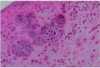

acute osteomyelitis

acute osteomyelitis

chronic osteomyelitis

chronic osteomyelitis

chronic osteomyelitis